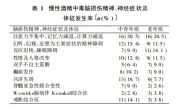

| 2021年7月26日 (一) 20:01 | 慢性酒精中毒症状.jpg (文件) |  |

56 KB | 77921020 | Uploaded with SimpleBatchUpload | 3 |